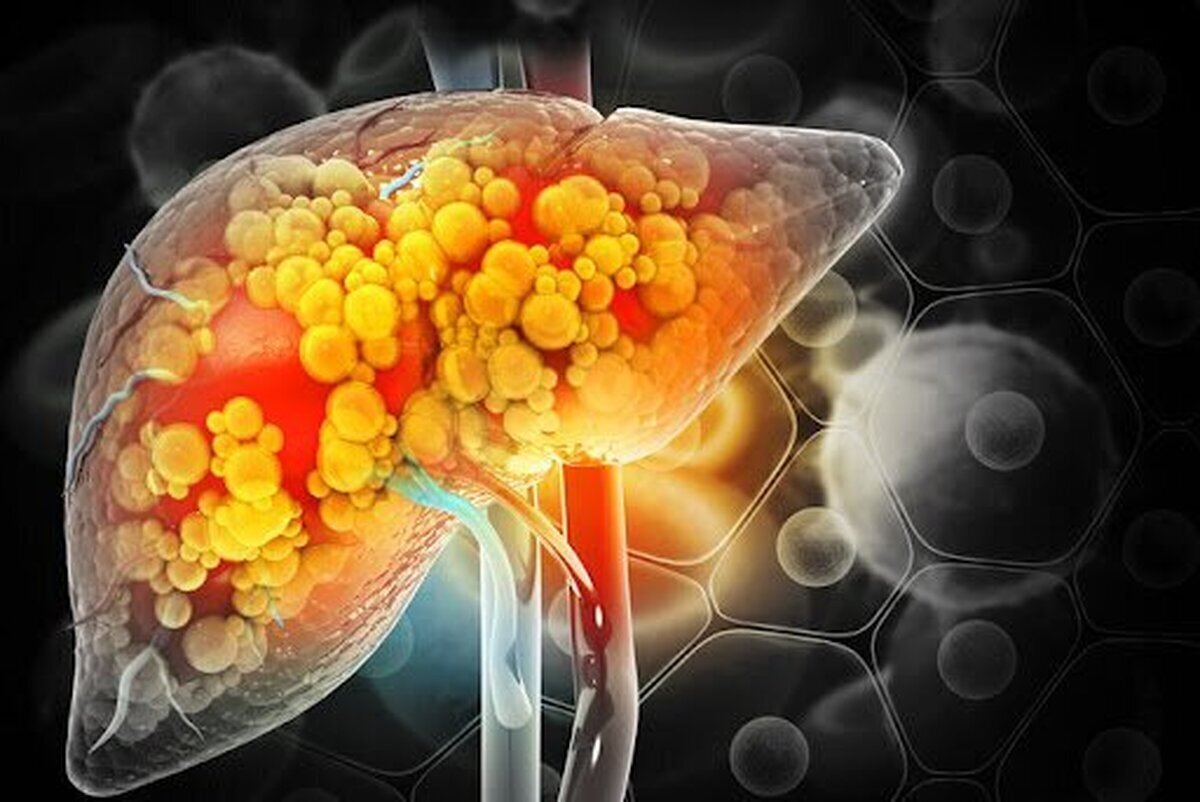

کبد چرب

آفتاب نیوز : مشکلات کبدی به دلایل مختلف ممکن است رخ دهد اما همیشه ناشی از مصرف الکل نیست. کبدچرب غیرالکلی نوع تهاجمی از بیماری کبد چرب است که می تواند باعث آسیب شدید کبد شده و بر سلامت کلی بدن تأثیر بگذارد. به نقل از مدیکال نیوز در حال حاضر هیچ درمان مؤثری برای بیماری کبد چرب غیرالکلی وجود ندارد اما یک مطالعه جدید نشان داد که ویتامین B ۱۲ و فولات می توانند به کاهش التهاب و زخم در افراد انسانی و مدل های حیوانی کمک کنند. مطالعه جدید مکانیسم های بیماری کبدچرب را مورد بررسی قرار داده و پی برده است که در این بیماری از انجام فعالیت یک پروتئین خاص موسوم به “سینتاکسین ۱۷” در از بین بردن سلول های مرده و ناسالم جلوگیری می شود. همچنین محققان دریافتند که ویتامین B ۱۲ و فولات برای افزایش سطح سینتاکسین ۱۷ عمل کرده و به از بین رفتن فیبروز (ضخیم شدن یا زخم) و التهاب کبد کمک می کنند. کبدچرب غیرالکلی می تواند باعث ایجاد زخم و آسیب دائمی کبد شود و خطر ابتلاء به سرطان کبد را افزایش دهد. محققان مطالعه حاضر دریافتند که افزایش در اسید آمینه هموسیستئین (HCY) همزمان با التهاب کبدی و فیبروز …

آفتاب نیوز : کبد یکی از مهم ترین اندام های بدن است که در قسمت راست بالای شکم زیر دیافراگم قرار دارد. این اندام نقش کلیدی در متابولیسم بدن ایفا می کند و مسئول سم زدایی تولید پروتئین های ضروری ذخیره انرژی تنظیم سطح قند خون و متابولیسم چربی ها است. همچنین کبد در تنظیم و حذف مواد زائد و دارو ها از جریان خون نقش حیاتی دارد. هرگونه اختلال در عملکرد کبد می تواند به مشکلات جدی سلامتی و حتی مرگ منجر شود. کبد چرب در اثر تجمع چربی در سلول های کبد ایجاد می شود. این بیماری معمولاً در چهار گرید طبقه بندی می شود که هر کدام ویژگی ها و علائم خاصی دارند. البته بسیاری از موارد کبد چرب علامتی بروز نمی دهد و به طور خاموش پیشروی می کند؛ بنابراین هر سال سلامتی اش را بررسی کنید ولو آن که هیچ کدام از علائم زیر را نداشته باشید. شایع ترین علامت کبد چرب بی علامت بودن آن است و بعد از آن علائم زیر ممکن است بروز کنند: گرید ۱: کبد چرب خفیف در این مرحله تجمع چربی در کبد کم است و معمولاً علائم خاصی ندارد. ممکن است فرد احساس خستگی یا سنگینی در ناحیه …

آفتابنیوز : کبدچرب غیر الکلی بر اثر تجمع چربی در سلولهای کبد به وجود میآید و در افرادی که دچار اختلال در متابولیسم بدن هستند و چربی و قند خونشان بالاست، بیشتر دیده میشود. البته فردی که به آن مبتلا میشود، زمینه ژنتیکی هم دارد. در این بیماری تری گلیسیریدی که در سلولها تجمع یافته از سلولهای کبدی خارج نمیشود و وقتی به تدریج چربی در سلولهای کبدی جمع میشود، اصطلاحا میگویند فرد دچار کبدچرب غیرالکلی شده است. تا این مرحله کبدچرب قابل درمان است، اما در صورتی که فرد متوجه نشود یا پیگیر درمان نباشد، وارد مرحله «سیروز» و بدخیمیهای کبدی میشود که درمان ندارد؛ زیرا سلولهای کبدی تخریب شده و راهی جز پیوند کبد باقی نمیماند. بنابر اعلام دفتر بهبود تغذیه جامعه وزارت بهداشت، متاسفانه یکی از مشکلات کبدچرب این است که نشانه خاصی ندارد و فقط با انجام آزمایش یا سونوگرافی میتوان این بیماری را تشخیص داد. البته برخی علائم در بیماران مبتلا ممکن است وجود داشته باشد که از جمله آن خستگی و درد در ناحیه بالا و سمت راست شکم است. ۷۰ درصد افراد دچار کبدچرب به اضافه وزن و چاقی مبتلا هستند و سابقه قند و چربی خون بالا دارند. در واقع کسانی که …

آفتابنیوز : شهرام آگاه درباره شایعترین بیماریهای کبدی در کشور اظهار کرد: کبد چرب شایعترین مشکل کبدی در کشور ما است که یک بیماری مزمن کبدی است و بهدلیل تجمع مقادیر زیاد چربی در سلولهای کبد به وجود میآید و در کشور ما نیز روند به رشدی دارد. علل اصلی بروز کبد چرب وی درباره علل اصلی بروز کبد چرب افزود: کبد چرب در پی زمینه ژنتیکی، رژیم غذایی ناسالم و نداشتن فعالیت بدنی ایجاد میشود. چاقی از عوامل اصلی بروز کبد چرب آگاه ادامه داد: چاقی یکی از دلایل مهم بروز کبد چرب به شمار میرود و ۸۰ درصد افرادی که مبتلا به کبد چرب هستند دچار چاقیاند، بنابراین درمان چاقی و کاهش وزن و ورزش کردن کمک زیادی به درمان کبد چرب میکند. مصرف داروها به درمان کبد چرب کمک میکند؟ فوقتخصص بیماریهای گوارش و کبد بزرگسالان با اشاره به اینکه هیچ داروی ثابت شدهای در جهان برای درمان کبد چرب وجود ندارد و داروهای موجود که از سوی پزشکان تجویز میشوند، تنها به درمان بیماری کمک میکنند، گفت: برخی افراد تصور میکنند که صرف مصرف دارو باعث درمان کبد چرب میشود در حالی که مصرف دارو در کنار رعایت رژیم غذایی مناسب و ورزش کردن میتواند به …

آفتابنیوز : محققان دانشگاه ویرجینیا بیش از ۱۷۰۰ بیمار را برای یک دوره چهار ساله، از جمله برخی از آنها را تا ۱۰ سال، تحت نظر قرار دادند. محققان دریافتند که بیماران مبتلا به فیبروز کبدی پیشرفته بیشتر با احتمال مرگ ناشی از خونریزی دستگاه گوارش یا تجمع مایعات در شکم و بدتر شدن عملکرد مغز به دلیل بیماری کبدی، روبرو هستند. «آرون سانیال»، سرپرست تیم تحقیق، گفت: «این اولین تصویر واضح از میزان واقعی پیامدها در افرادی است که بیماری کبد چرب غیرالکلی) دارند. این مطالعه بر ضرورت غربالگری بیماریهای کبدی تاکید دارد.» بسیاری از مردم میدانند که مصرف بیش از حد الکل باعث بیماریهای کبدی میشود. با این حال، یک چهارم بزرگسالان در سراسر جهان به بیماری کبد چرب غیرالکلی مبتلا هستند، عارضهای که در آن چربی اضافی در کبد ذخیره میشود و بیشتر با چاقی و دیابت ارتباط دارد تا مصرف الکل. اکثر مردم نمیدانند که مبتلا به بیماری کبد چرب غیرالکلی هستند یا در معرض خطر بالای ابتلاء به آن قرار دارند. در صورت عدم درمان، بیماری میتواند تا حد زیادی پیشرفت کند، و تجمع چربی در کبد میتواند باعث التهاب، زخم (معروف به فیبروز) و سیروز کامل کبدی شود که منجر به آسیب دائمی به …